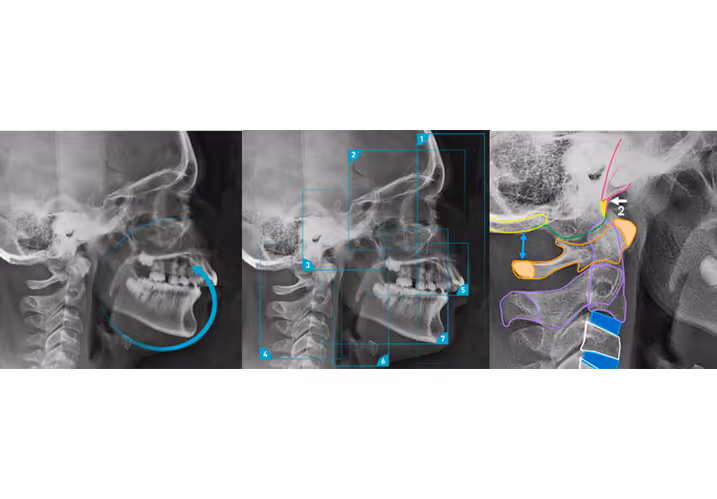

Les clichés obtenus sont ensuite analysés à l’aide de tracés céphalométriques permettant d’établir des mesures précises sur l’orientation des structures osseuses et dentaires. Ces mesures aident à quantifier les déséquilibres squelettiques et à prévoir l’évolution de la croissance chez les patients en développement.

L’interprétation des téléradiographies repose sur des repères anatomiques précis permettant de réaliser des mesures angulaires et linéaires. Il existe de nombreuses étude céphalométrique que nous ne détaillerons pas ici.